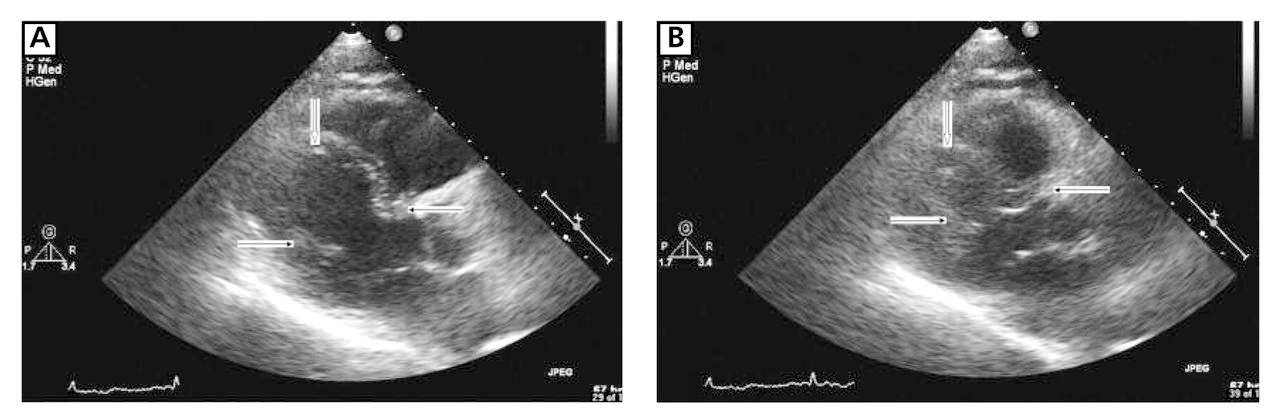

The patient's cardiac biomarkers quickly returned to normal, and a repeated transthoracic echocardiogram 3 days later (day 5) revealed nearly complete resolution of myocardial wall–motion abnormalities (Figure 4). The patient was discharged from the hospital on day 6, and the regimen of metorprolol, 100 mg/d, and candesartan, 8 mg/d, was continued. A repeated ECG approximately 3 weeks later demonstrated resolution of anterior ST-segment elevation and deep, diffuse T-wave inversions in the inferior and precordial leads (Figure 5). Three months after hospital admission, the patient's ECG results had returned to normal (Figure 6).

Long-axis precordial end diastolic (A) and end systolic (B) views obtained on day 5 of hospital admission demonstrate near-complete resolution of apical dyskinesia and distal inferior and anterior wall akinesia. The ejection fraction was estimated at 60% to 65%.